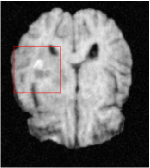

All the experiments are implemented on a Windows workstation with Intel Core i9 CPU at 3.3GHz and an Nvidia GTX-1080Ti GPU with 11GB of graphics card memory via TensorFlow Abadi et al. (2016). The parameters in the proposed network are initialized by using Xavier initialization Glorot and Bengio (2010). We trained the meta-learning network with four tasks synergistically associated with four different CS ratios: 10%, 20%, 30%, and 40%, and test the well-trained model on the testing dataset with the same masks of these four ratios. We have 300 training data for each CS ratio, which amount to total of 1200 images in the training dataset. The results for and MR reconstructions are shown in Tables 5.4 and 5.4 respectively. The associated reconstructed images are displayed in Figures 1 and 3. We also test the well-trained meta-learning model on unseen tasks with radio masks for skewed ratios: 15%, 25%, 35%, and random Cartesian masks with ratios 10%, 20%, 30% and 40%. The task-specific parameter for the unseen tasks are retrained for different masks with different sampling ratios individually with fixed task-invariant parameters . In this experiments, we only need to learn for three skewed CS ratios with radio mask and four regular CS ratios with Cartesian masks. The experimental training proceed on less data and iterations, where we performed on 100 MR images with 50 epochs. For example, for reconstructing MR images with CS ratio 15% radio mask, we fix the parameter and retrain the task-specific parameter on 100 raw data with 50 epochs, then test with renewed on our testing data set with raw measurement that sampled from radio mask with CS ratio 15%. The results associated with radio masks are shown in Table 5.4 and 5.4, Figure 2 and 4 for and images respectively. The results associated with Cartesian masks are list in Table 5.4 and reconstructed images are displayed in Figure 5.

Qualitative comparison between conventional and Meta-learning methods are shown in Figure 1 and 3, which display the reconstructed MR images of the same slice for T1 and T2 respectively, we label the zoomed-in details of HGG in the red boxes. We observe the evidence that conventional learning is more blurry and lost sharp edges, especially in lower CS ratios. From the point-wise error map, we find meta-learning has the ability to reduce noises especially in some detailed and complicated regions comparing to conventional learning.

In this section, we test the generalizability of the proposed model that tests on unseen tasks. We fix the well-trained task-invariant parameter and only train for sampling ratios 15%, 25% and 35% with radio masks and sampling ratios 10%, 20%, 30% and 40% with Cartesian masks. In this experiment, we only used 100 training data for each CS ratio and apply a total of 50 epochs. The averaged evaluation values and standard deviations are listed in Table 5.4 and 5.4 for reconstructed T1 and T2 brain images respectively that proceed with radio masks, and Table 5.4 shows the qualitative performance for reconstructed T2 brain image that applied random Cartesian sampling masks. In T1 image reconstruction results, meta-learning improved 1.6921 dB in PSNR for 15% CS ratio, 1.6608 dB for 25% CS ratio, and 0.5764 dB for 35% comparing to the conventional method, which in the tendency that the level of reconstruction quality for lower CS ratios improved more than higher CS ratios. A similar trend happens in T2 reconstruction results with different sampling masks. The qualitative comparisons are illustrated in Figure 2, 4 and 5 for T1 and T2 images tested in skewed CS ratios in radio masks, and T2 images tested in Cartesian masks with regular CS ratios respectively. In the experiments that conducted with radio masks, meta-learning is superior to conventional learning especially at CS ratio 15%, one can observe that the detailed region in red boxes keeps edges and is more close to the true image, while conventional method reconstructions are hazier and lost details in some complicated tissue. The point-wise error map also indicates that Meta-learning has the ability to suppress noises.